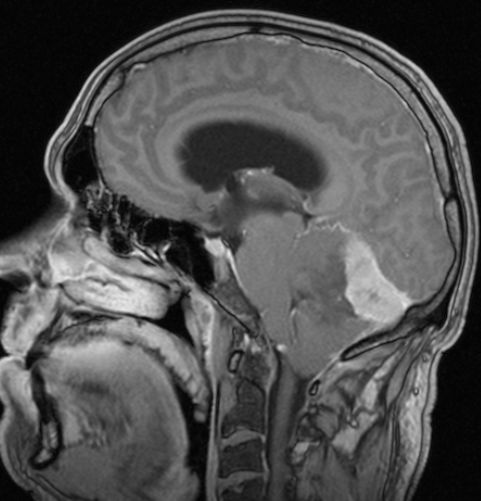

| Meningeom frontal |

59-jähriger Patient, der wegen AV-Block in die Kardiologie eingeliefert wurde. Das CT zeigt einen hirninvasiven Tumor, der die Mittellinie überschreitet. Postoperativ ergab sich ein Meningeom 2. Grades. | . |